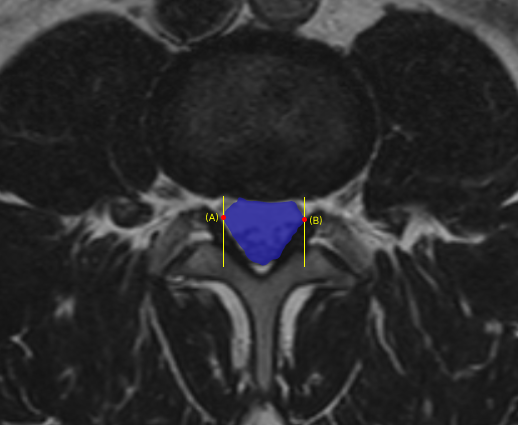

Designing and implementing three new sets of DICOM series (Summary, Sagittal, Axial) enhanced by AI to be viewed alongside original images, optimizing visual appeal and user experience through collaboration with physician consultants and detailed design systems, ultimately bridging the gap between machine learning outputs, customer requirements, and business goals.

A similar process started in parallel to create AI-enriched DICOM images for an application in aneurysm. I used a similar approach and conducted weekly design critiques with physicians in order to refine the designs.